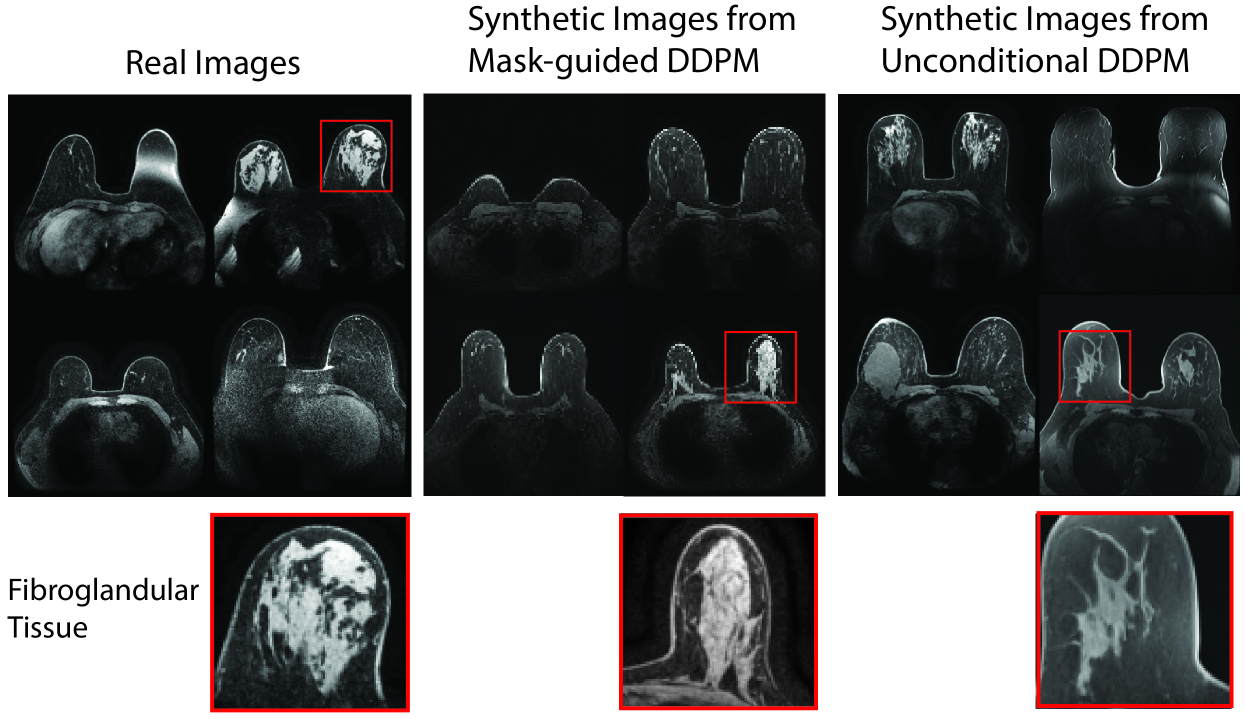

We first attempted to use the common Fréchet Inception Distance (FID) [Heusel et al.(2017)Heusel, Ramsauer, Unterthiner, Nessler, and Hochreiter] as a metric for generated image quality/realism compared to real data. Since the original FID utilizes a CNN image encoder pre-trained on natural images, which may fail to capture the characteristics of medical images, we propose to instead use an encoder trained on the corresponding medical image dataset. We observe that samples generated from both the segmentation-guided and unconditional diffusion models achieve promising results, (e.g., for breast MRI), yet the CNN-based FID fails to capture the global feature of anatomical realism that can differ in images generated by these models (e.g., fibroglandular tissue as shown in Fig. LABEL:fig:eg_imgs).

Denoising diffusion probabilistic models [Ho et al.(2020)Ho, Jain, and Abbeel] (DDPMs, or just “diffusion models”) have shown extensive promise in medical image analysis and beyond [Kazerouni et al.(2023)Kazerouni, Aghdam, Heidari, Azad, Fayyaz, Hacihaliloglu, and Merhof] due to their ability to generate high-quality, high-resolution images. However, standard generative models like DDPMs can still fail to create anatomically plausible tissue (Fig LABEL:fig:eg_imgs). Our proposed solution is to incorporate anatomical information as a prior for image generation via a segmentation mask for different types of tissue, organs, etc., providing the network with a more direct learning signal for anatomical realism. Image-space-based diffusion models are especially amenable for strict segmentation guidance because a conditioning mask can be used as-is for every small step of the denoising process, with no conversion to some abstract latent space as in latent diffusion models (or GANs) where complex spatial conditions may be lost. In this paper, we introduce an image-space diffusion model for segmentation-guided image generation: Segmentation-Guided Diffusion.

fig:eg_imgs